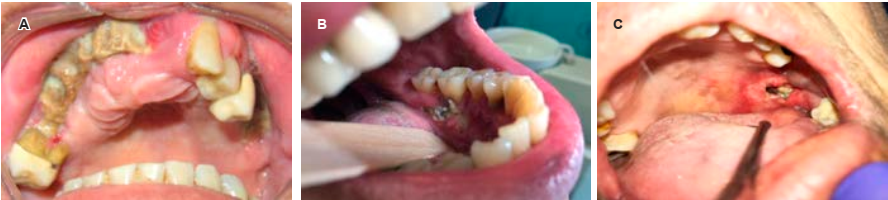

Recientemente se utilizan los bisfosfonatos, medicamentos que sirven de apoyo en el tratamiento. Debido a que inhiben la producción de osteclastos y disminuyen la reabsorción ósea, son utilizados para controlar las metástasis óseas y osteólisis en el cáncer avanzado o descalcificación por cáncer. Existen bifosfonatos orales e intravenosos (ácidos zoledrónico y pamidrónico). Los intravenosos pueden producir el efecto secundario adverso denominado osteonecrosis de los maxilares. El factor de riesgo asociado para que se desarrolle osteonecrosis de los maxilares es traumatismo óseo, siendo las extracciones dentales de tipo quirúrgico las más comunes. En ocasiones, la necrosis ósea se puede presentar de manera espontánea. El odontólogo deberá estar informado de la osteonecrosis asociada a los bifosfonatos y también en contacto con el médico oncólogo.8,9 Se muestran casos de osteonecrosis por en las Figuras 3 y 4.

Figura 3 A y B) Casos de necrosis y exposición ósea maxilar y mandíbula con posterior a extracción dental. C) Caso de necrosis y exposición ósea maxilar de forma espontánea.